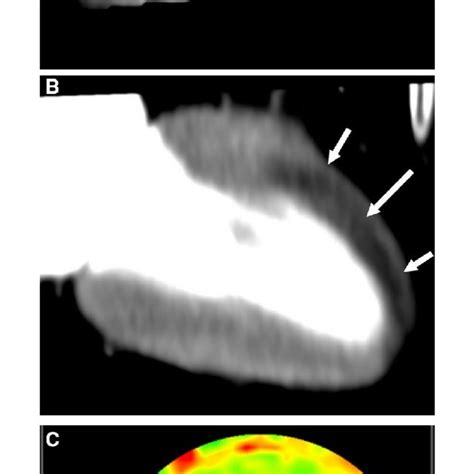

So, what exactly is CT-FFR , and why should you care about its normal values? CT-FFR stands for Computed Tomography derived Fractional Flow Reserve. Basically, it’s a revolutionary non-invasive way to assess the severity of blockages in your coronary arteries. Before CT-FFR came along, doctors often had to rely on invasive procedures like cardiac catheterization to measure FFR, which involves inserting a wire into the heart. That sounds pretty intense, right? But now, with CT-FFR, we can get incredibly accurate information about blood flow through your heart arteries just from a standard CT scan. This is a game-changer , guys! It helps doctors pinpoint exactly where a blockage might be causing problems and how significant that blockage is in terms of restricting blood flow. The goal here is to identify if a narrowed artery is actually reducing blood flow enough to cause symptoms like chest pain or shortness of breath, or if it’s just a minor narrowing that isn’t a big concern. Knowing these normal values is key because they act as a benchmark, a standard against which your specific scan results are compared. Without these benchmarks, the scan data would just be a bunch of numbers with no real context. So, understanding CT-FFR normal values is essentially understanding what a healthy heart’s blood flow looks like, allowing for precise diagnosis and personalized treatment plans. It’s all about making smarter, less invasive decisions for better heart health outcomes.

Alright, let’s get down to the nitty-gritty: what are the normal CT-FFR values ? This is the golden question, right? Generally, a CT-FFR value greater than or equal to 0.80 is considered normal. This means that the pressure drop across a section of the coronary artery is minimal, indicating that blood flow is not significantly restricted. Think of it as a green light for that part of your artery – no major traffic jams! On the flip side, a CT-FFR value less than 0.80 is typically considered abnormal and suggests that there is a significant blockage causing a substantial pressure drop, which can impede blood flow to the heart muscle. This 0.80 threshold is widely accepted and used in clinical practice and research because it has been validated to correlate well with invasive FFR measurements and predict adverse cardiovascular events. However, it’s super important to remember that these are general guidelines. The interpretation of your specific CT-FFR result should always be done by a qualified healthcare professional, like your cardiologist. They will consider your individual medical history, other test results, and the specific clinical context when evaluating your scan. Sometimes, borderline values might require further investigation or monitoring. Don’t try to self-diagnose based on these numbers, guys! They are powerful tools when used correctly by experts. The beauty of CT-FFR is its ability to distinguish between anatomical blockages seen on a standard CT angiogram and functional blockages that actually cause physiological problems. A high-grade anatomical blockage doesn’t always mean reduced blood flow, and conversely, a less severe-looking blockage might be functionally significant. CT-FFR helps cut through that ambiguity, giving doctors a clearer picture. So, while 0.80 is our magic number for normal, remember it’s part of a bigger diagnostic puzzle.

The 0.80 threshold for CT-FFR isn’t just pulled out of thin air, guys. It’s a number that has been rigorously studied and validated through numerous clinical trials. This specific value represents a point at which a significant pressure gradient across a coronary artery stenosis is likely to impair myocardial blood flow and potentially lead to ischemia (lack of oxygen to the heart muscle). In simpler terms, when the CT-FFR drops below 0.80, it strongly suggests that the blockage is severe enough to warrant attention. This threshold was established based on its strong correlation with invasive FFR measurements, which are considered the gold standard for assessing the hemodynamic significance of coronary artery lesions. Studies like the PLATFORM trial have been instrumental in demonstrating the accuracy and clinical utility of CT-FFR compared to standard CT angiography alone. By establishing this clear, evidence-based threshold, CT-FFR provides a reliable and objective measure for clinicians. It helps them make critical decisions about patient management, such as whether a patient would benefit from revascularization procedures like angioplasty or stenting. A value above 0.80 indicates that the blood flow is likely adequate, and the stenosis, even if visible, is not hemodynamically significant, meaning invasive procedures might not be necessary and conservative management could be appropriate. This ability to differentiate functional significance is a massive advantage , reducing unnecessary invasive procedures, associated risks, and healthcare costs, while ensuring that patients who truly need intervention receive it promptly. It’s all about precision medicine – getting the right treatment for the right patient at the right time, guided by robust data like this 0.80 benchmark.